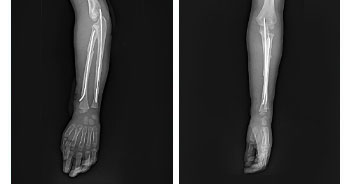

ADVANCED TRAUMA CARE

In any Trauma care center to receive and resuscitate the patient and to save life is our first priority. Saving the limb and other important organs is the next priority.

The hospital follows the principle of Triage, where by the patients are segregated by the surgeons as to have life threatening, limb threatening and other injuries depending on the type of injury, and are given treatment priority as the situation demands. To achieve this, a well-equipped intensive care unit and properly trained surgeons, anesthetists & Paramedical staffs are available, round the clock. Advance techniques in body warming, Sequential compression device, Alpha beds, and remote controlled ICU cots are available keeping the patients comfort in mind. Defibrillators, Ventilators, ABG analyzers, Cardio machine etc., are available to diagnose and prevent major complications.

• Trauma Surgery